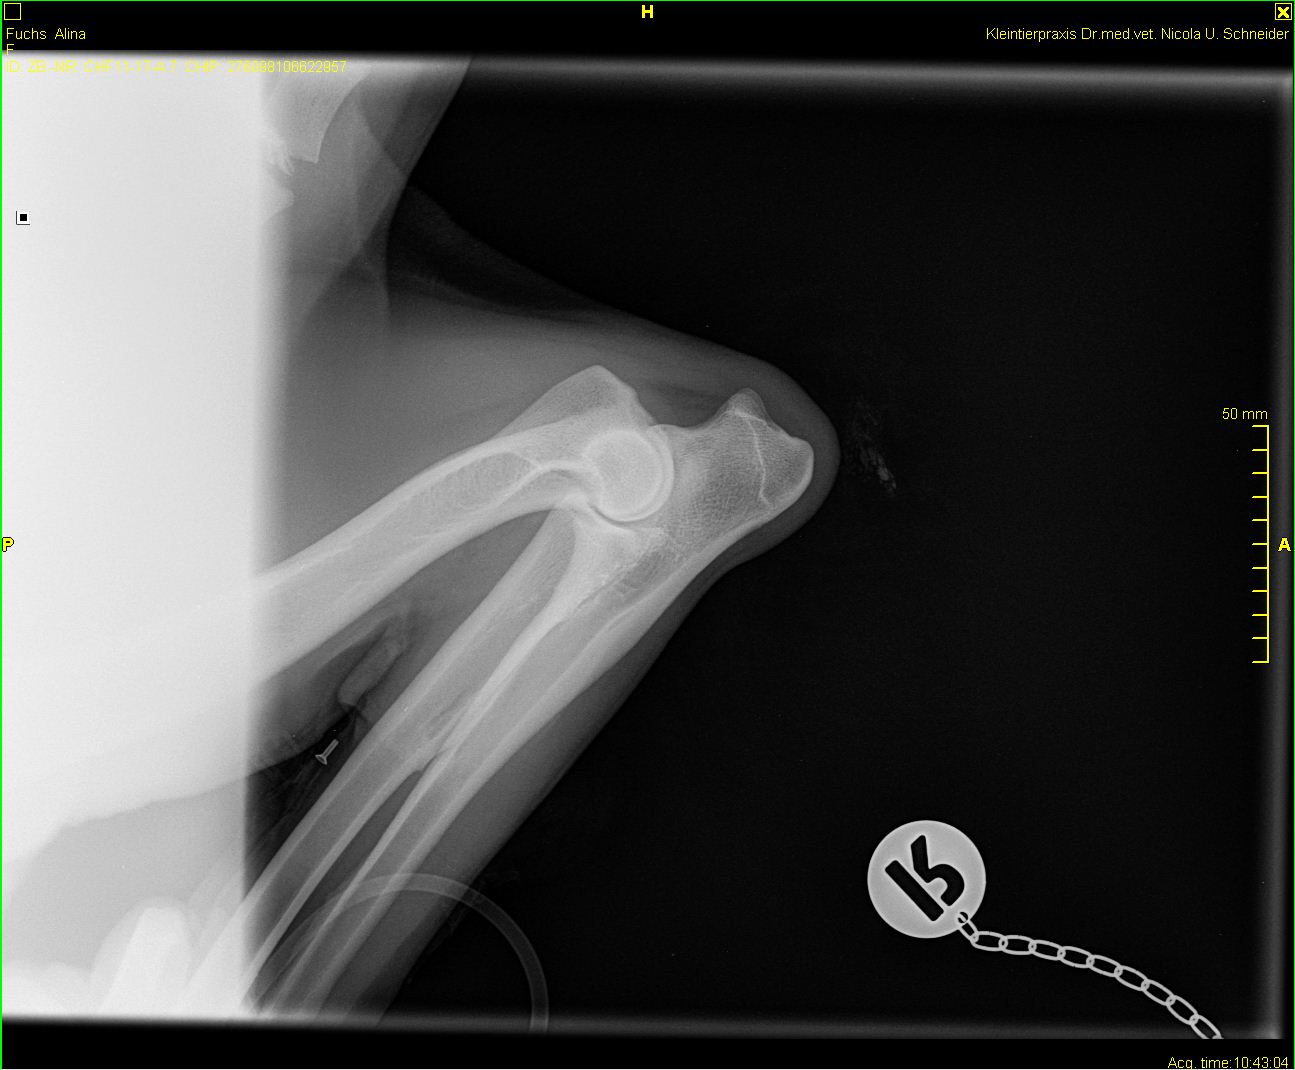

Alina - ED-Röntgen

-Alina-ed-links